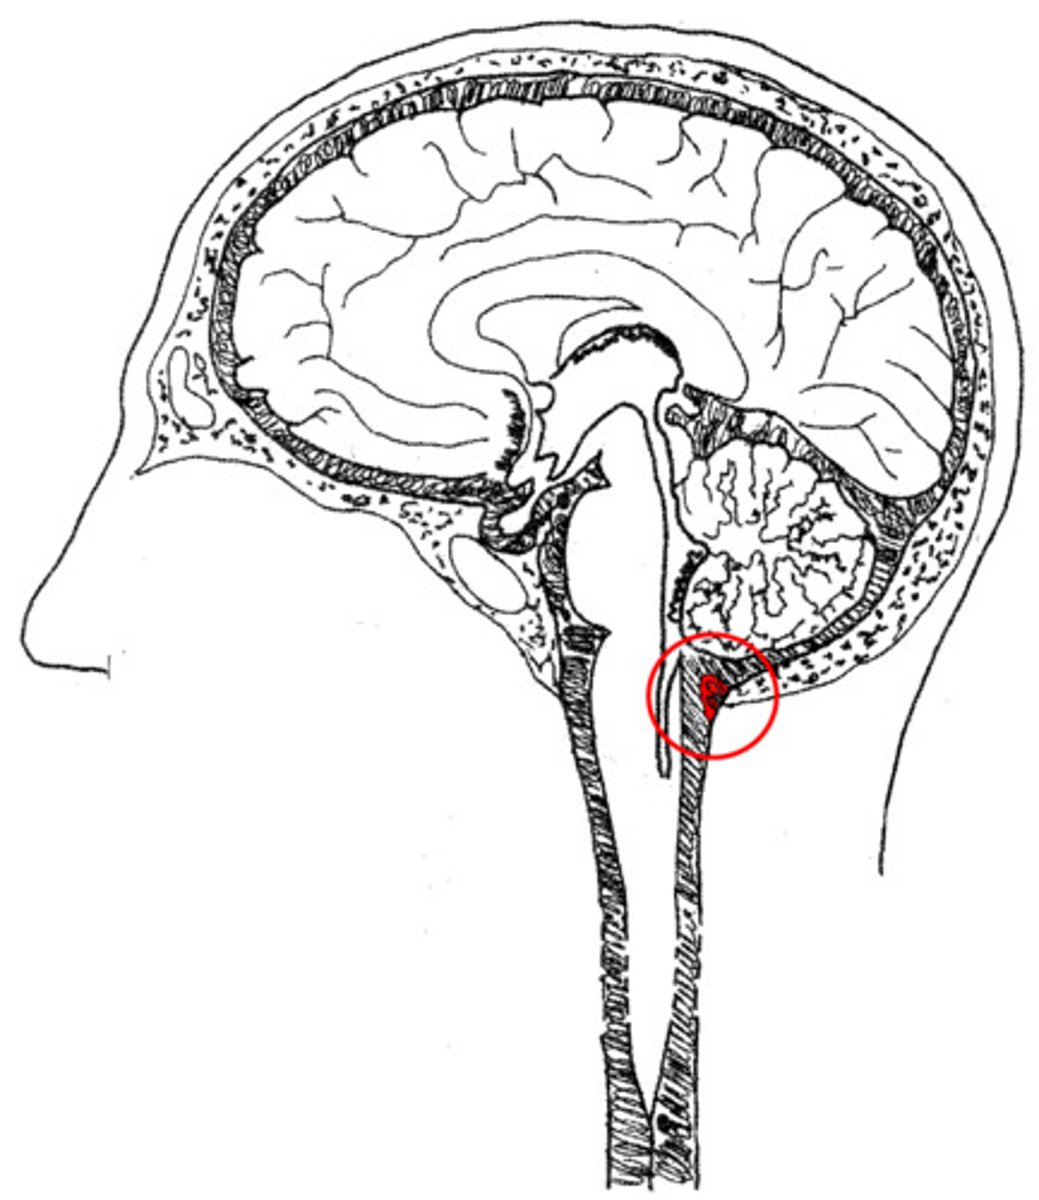

cervicomedullary junction

transition between the medulla oblongata and upper cervical spinal cord (C1-C2) that is located at the level of the foramen magnum

*houses ascending/descending tracts (decussation) and nuclei that influence breathing, CV control, and CN 9-12

*orange line on picture

tonsillar herniation

herniation of the brain where cerebellar tonsils descend through the foramen magnum